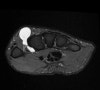

MRI : 손목 결절종(Wrist ganglion)